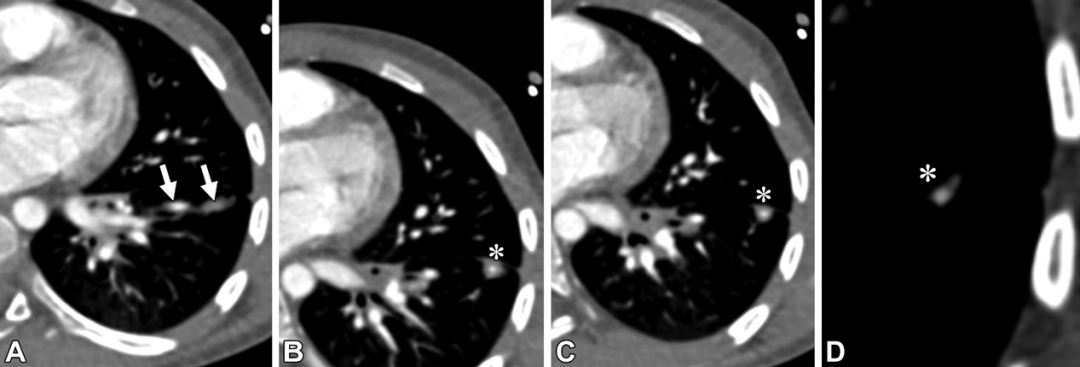

PAVM。轴位CT图,32岁男性,遗传性出血性毛细血管扩张症,因右向左分流导致的慢性低氧血症。(A,B)轴位CT图,可见右肺下叶PAVM的病灶(白色信号)及引流静脉(白色箭头)。(C,D)轴位CT图,可见供血动脉大于3mm(白色箭头)。(E)右肺下叶另见一个PAVM,在供血动脉及引流静脉之间的磨玻璃密度影(白色圆圈),提示显微镜下毛细血管扩张。(F,G)一个复杂的PAVM位于左肺下叶,可见三个供血动脉(F图中白色虚线箭头)以及一个粗大的引流静脉(白色星号),注意观察引流静脉比供血动脉大。